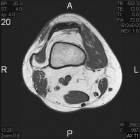

34 year old female with a three year history of right knee mass

Zoom image: Radiological image Radiological image.